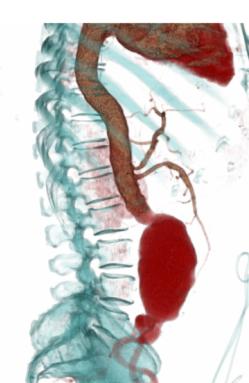

增强后:腹主动脉下段至左右髂总动脉上端明显扩张,最宽处约6.8cm,上下径约为13cm,成瘤样改变,边界清楚,形态规整。

1.腹主动脉瘤。(腹主动脉下段至左右髂总动脉上端)

后重建图像就是直观